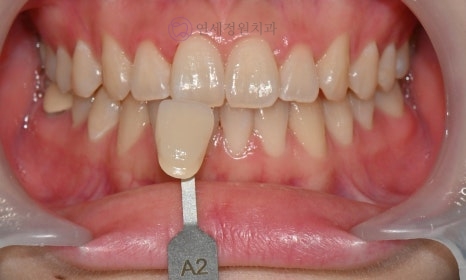

Before starting the teeth whitening process, the color of your teeth will be assessed. A shade guide will be used to record the tooth color; the shade guide is a specific indicator that expresses the degree of lightness or darkness of the teeth in stages. As the letters increase numerically, the color becomes darker. Tooth colors are classified into 16 stages, ranging from B1 to C4 (B1-A1-B2-D2-A2-C1-C2-D4-A3-D3-B3-A3.5-B4-C3-A4-C4). The closer to B1, the brighter the natural tooth color, and the closer to C4, the darker the color.

Before and After

Before Shade: A2 / After Shade: B1